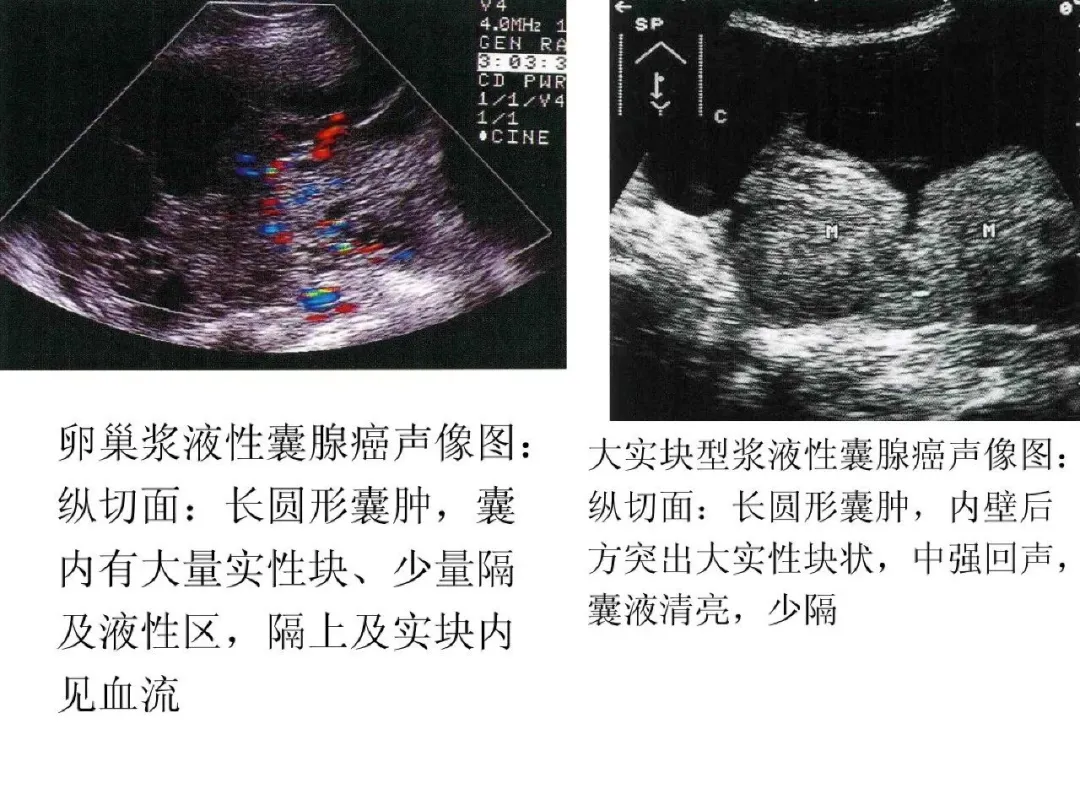

浆液性囊腺癌

●是临床上最常见的卵巢恶性肿瘤,约占卵巢恶性肿瘤的40%-60%,半数为双侧,乳头可穿过瘤壁向外生长。

●二维超声图特征:呈圆形或椭圆形,表面光滑或不规则;囊壁厚;多显示囊实性,囊液清亮或混浊,内壁有毛刷状小乳头,强回声粗大乳头,实质部分呈强回声或低回声;血流较丰富;多伴有腹水。